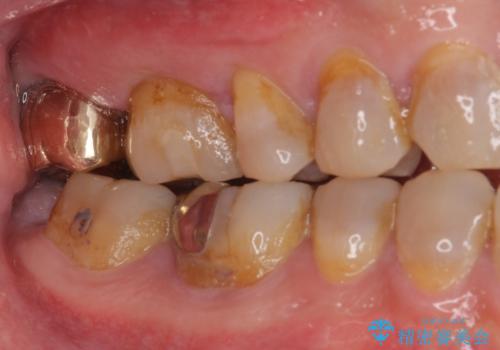

ゴールドインレーは銀歯のインレーやセラミックインレーと比べ、「技工操作の精度が高く、適合が著しく良い」というメリットがあります。特に上の奥歯は歯科医師の操作が行いにくいため、「適合の良さ」は再治療のリスクを防ぐ上でとても重要な要素となります。

上の奥歯は金属色が見えることもないため、審美的な問題は全くありません。

咬み心地はとても良好で、全く違和感がなく、患者様には大変満足していただきました。